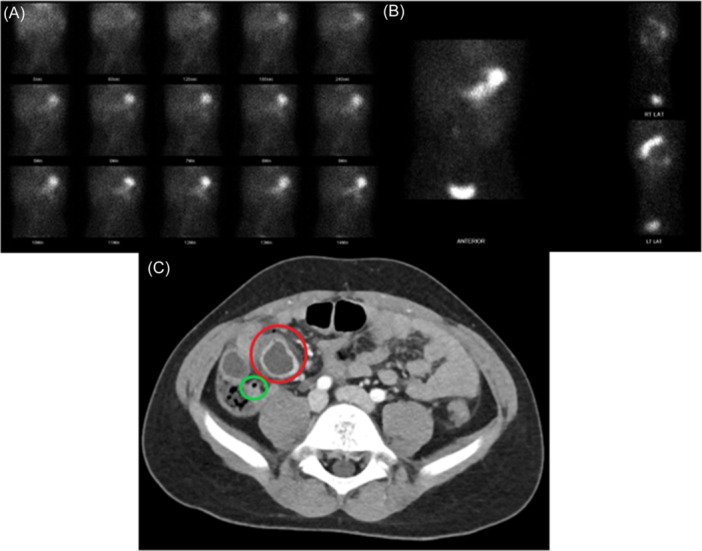

Abstract Image